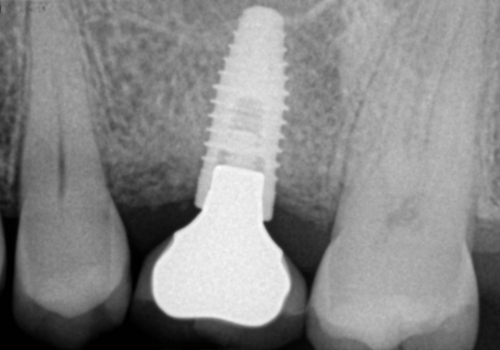

Stomatologiyanın təməl vəzifələrindən biri, itirilmiş dişlərin funksiya və estetik olaraq təbiiyə ən yaxın şəkildə bərpa edə bilməkdir. Dişsizliyin estetik və funksional olaraq yüksək səviyyədə reabilitasiyası, pasiyentlərin çeynəmə, danışma və gülmə kimi funksiyalarını qüsursuz icra edə bilməsi baxımından çox önəmlidir. Diş implantları xüsusi texnologiya hazırlanaraq, itirilmiş dişin bərpası üçün tətbiq edilən süni diş kökləridir. Bu metod təbiiyə ən yaxın bərpanı vəd edən müalicə metodu kimi uzun illərdən bəri beynəlxalq miqyasda geniş tətbiq olunur. İmplantasiya, bu işin peşəkarı yüksək ixtisaslı mütəxəssis tərəfindən qısa bir müddət davam edən prosedur vasitəsilə ağrısız, qısa müddətə və həyati funksiyaların məhdudlaşmaması şərti ilə həyata keçirilən müalicə üsuludur.

Dental implantlar əsasən titandan hazırlanır. Bu materialdan hazırlanmasının ən başlıca səbəbləri, bu metalın orqanizm tərəfindən rədd edilməməsi, heç bir allergik reaksiyaya səbəb olmaması və bu təyinat üçün yetərli möhkəmliyinin olmasıdır. Diş implantları vasitəsilə, tək diş əksikliyindən, çoxsaylı diş əksikliyi və tam dişsizlik halları funksional və estetik bərpa edilə bilir. İmplantın üzərinə hazırlanan diş konstruksiyaları müvafiq vəziyyətlərdə implantların tətbiqi ilə eyni gündə və ya müəyyən bir sağalma dövrünün keçməsindən sonra hazırlana bilir. İmplantların istismar müddəti, doğru planlama və icraat həyata keçirildiyində, eyni zamanda yetərli gigiyenik qulluq şəraitində bir neçə on illik bir periyodu əhatə edə bilir.